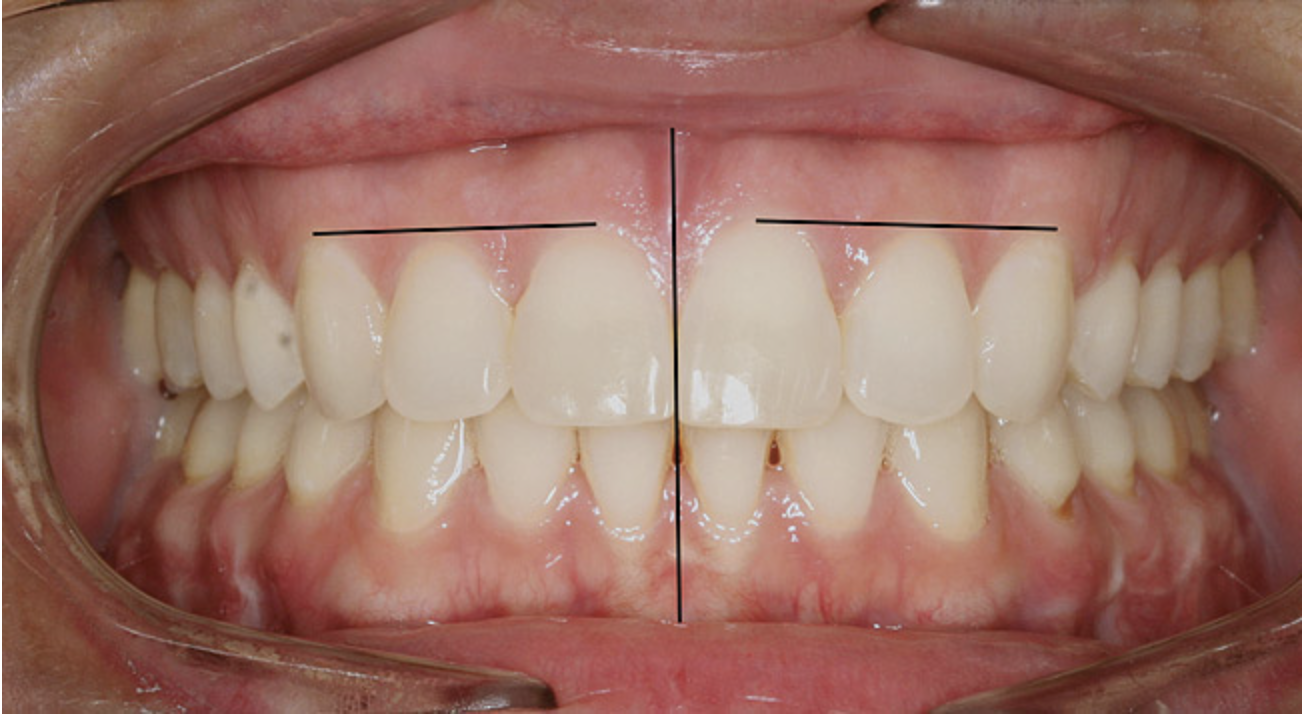

Figure 8  Intraoral view of the occlusion of patient from Figure 7 after retreatment. The occlusion is adequate to finish with equilibration.

Figure 8